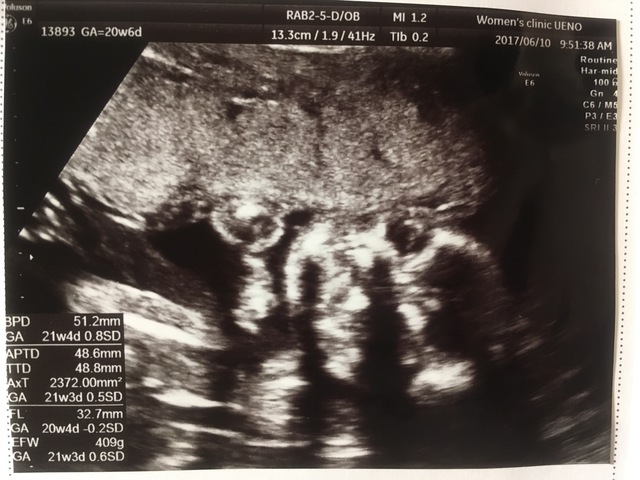

20週2日(20w2d・男の子)|はぎくみ さん(25歳)

エコー写真撮影時のエピソード:

この日初めて背骨が見えてすごく感動したのを覚えています。それまではずっと丸が二つくっついたようなドラえもんみたいな形のエコー写真だったので、もうこんなにおおきくなったんだなぁって。人間らしくなってきたんだなぁと。

それなのにお家に帰ってから旦那と母に見せたら怖い!ガイコツみたい!と言われ怒りました(笑)